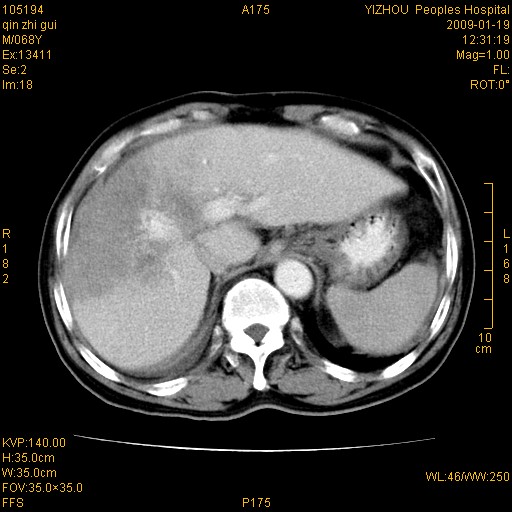

以下是引用随光逐影在2009-1-21 16:11:00的发言:[br]1)考虑肝右叶肝癌并肝静脉及门静脉瘤栓形成。2)肝硬化,少量腹水。3)胆囊炎。4)右侧少量胸腔积液。

病灶外缘凹凸不平,平扫低密度,增强动脉期有强化,门脉早显,静脉期及延期呈延迟强化,结合病史考虑右肝前叶巨块型肝癌可能性大,强化表现不除外胆管细胞癌